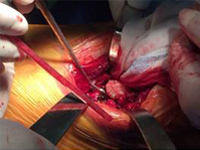

術中